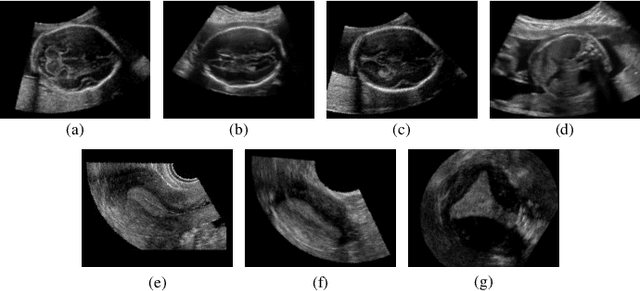

Abstract:The 3D ultrasound (US) entrance inspires a multitude of automated prenatal examinations. However, studies about the structuralized description of the whole fetus in 3D US are still rare. In this paper, we propose to estimate the 3D pose of fetus in US volumes to facilitate its quantitative analyses in global and local scales. Given the great challenges in 3D US, including the high volume dimension, poor image quality, symmetric ambiguity in anatomical structures and large variations of fetal pose, our contribution is three-fold. (i) This is the first work about 3D pose estimation of fetus in the literature. We aim to extract the skeleton of whole fetus and assign different segments/joints with correct torso/limb labels. (ii) We propose a self-supervised learning (SSL) framework to finetune the deep network to form visually plausible pose predictions. Specifically, we leverage the landmark-based registration to effectively encode case-adaptive anatomical priors and generate evolving label proxy for supervision. (iii) To enable our 3D network perceive better contextual cues with higher resolution input under limited computing resource, we further adopt the gradient check-pointing (GCP) strategy to save GPU memory and improve the prediction. Extensively validated on a large 3D US dataset, our method tackles varying fetal poses and achieves promising results. 3D pose estimation of fetus has potentials in serving as a map to provide navigation for many advanced studies.